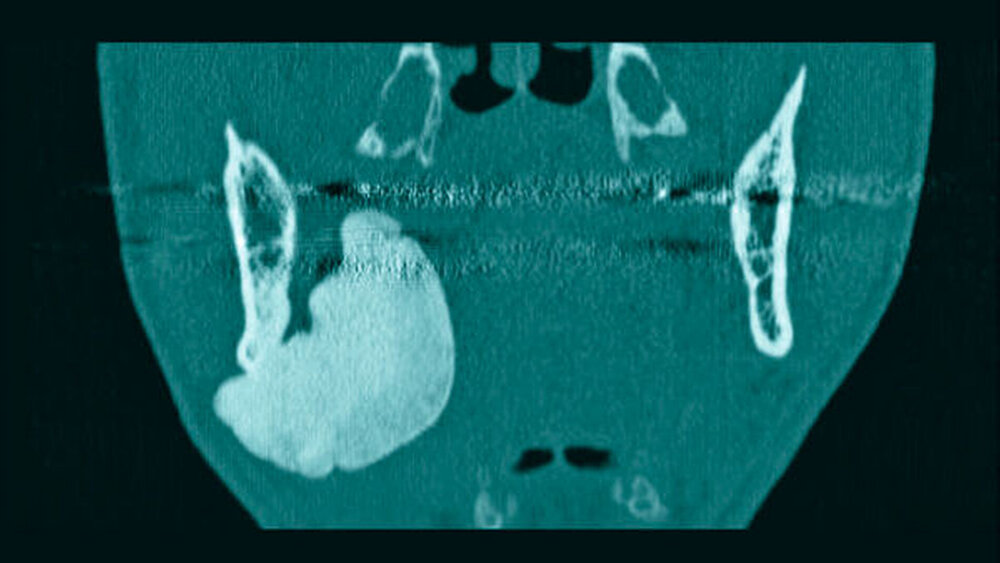

Im mitgebrachten alio loco erstellten Orthopantomogramm war eine gut abgrenzbare, ovale, homogene Verschattung zu sehen, welche sich im Bereich des rechten Kieferwinkels, in dorsaler und kranialer Richtung über diesen hinaus sowie im Bereich des aufsteigenden Unterkieferastes bis kaudal unter die Incisura semilunaris erstreckte (Abbildung 1). Computertomografisch war ausgehend von der medialseitigen Corticalis des Angulus mandibulae rechts eine irregulär, angedeutet rundlich konfigurierte, glatt begrenzte knöcherne Raumforderung von circa 4,4 x 3,3 x 4,7 cm Größe zu sehen (Abbildungen 2 und 3). Diese führte zu einer Verlagerung der Anatomie, insbesondere zu einer Vorwölbung der rechtsseitigen Oropharynxseitenwand (Abbildung 4). Es bestanden keine Hinweise auf eine knöcherne Destruktion oder auf eine Lagebeziehung zu einem Zahn.